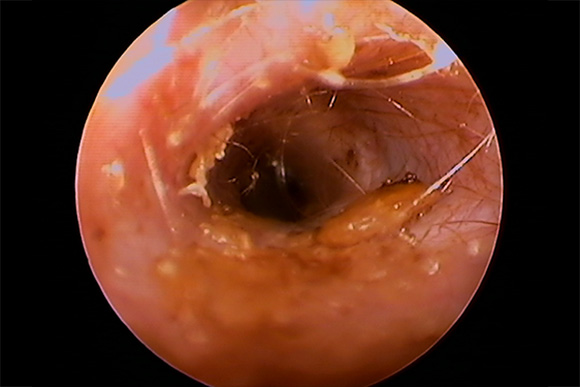

耳内視鏡(ビデオオトスコープ)で見た耳の状況

軽度~重度の症状の耳

犬の耳 1 犬の耳 2

犬の耳 2 猫の耳 1